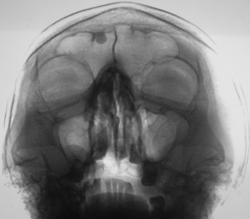

Иллюстрации 1, 2. На цифровой флюорограмме придаточных полостей носа, произведенной в прямой стандартной проекции в носо-подбородочном положении, в лобной пазухе, больше справа определяется тень значительной интенсивности, с довольно ровными, четкими контурами, однородной структуры. Интерпретация данной тени сложности не вызвала, так как по своим скиалогическим характеристикам представляет типичную остеому, а с учетом «излюбленной» локализации, дифференциально – диагностических трудностей не возникло.

.........."Иллюстрации 1, 2. На цифровой флюорограмме придаточных полостей носа, произведенной в прямой стандартной проекции в носо-подбородочном положении, в лобной пазухе, больше справа определяется тень значительной интенсивности, с довольно ровными, четкими контурами, однородной структуры. Интерпретация данной тени сложности не вызвала, так как по своим скиалогическим характеристикам представляет типичную остеому, а с учетом «излюбленной» локализации, дифференциально – диагностических трудностей не возникло."..... Как все догадались, это цитата из выше опубликованного поста ув. Валентина Львовича, она также подходит и к моему наблюдению.